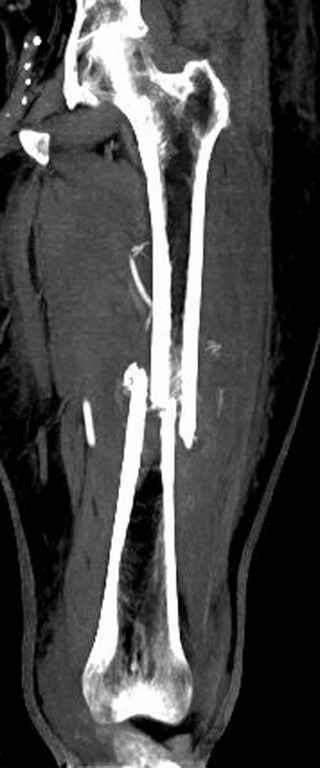

Здесь случай 66 летней пациентки со спонтанными болями в левой нижней

конечности, обратилась в приемное, сделаны снимки бедра и КТ.

Патологический перелом бедра, конечность на вытяжении.

Имя     : Pathologic Femur CT 1.jpg